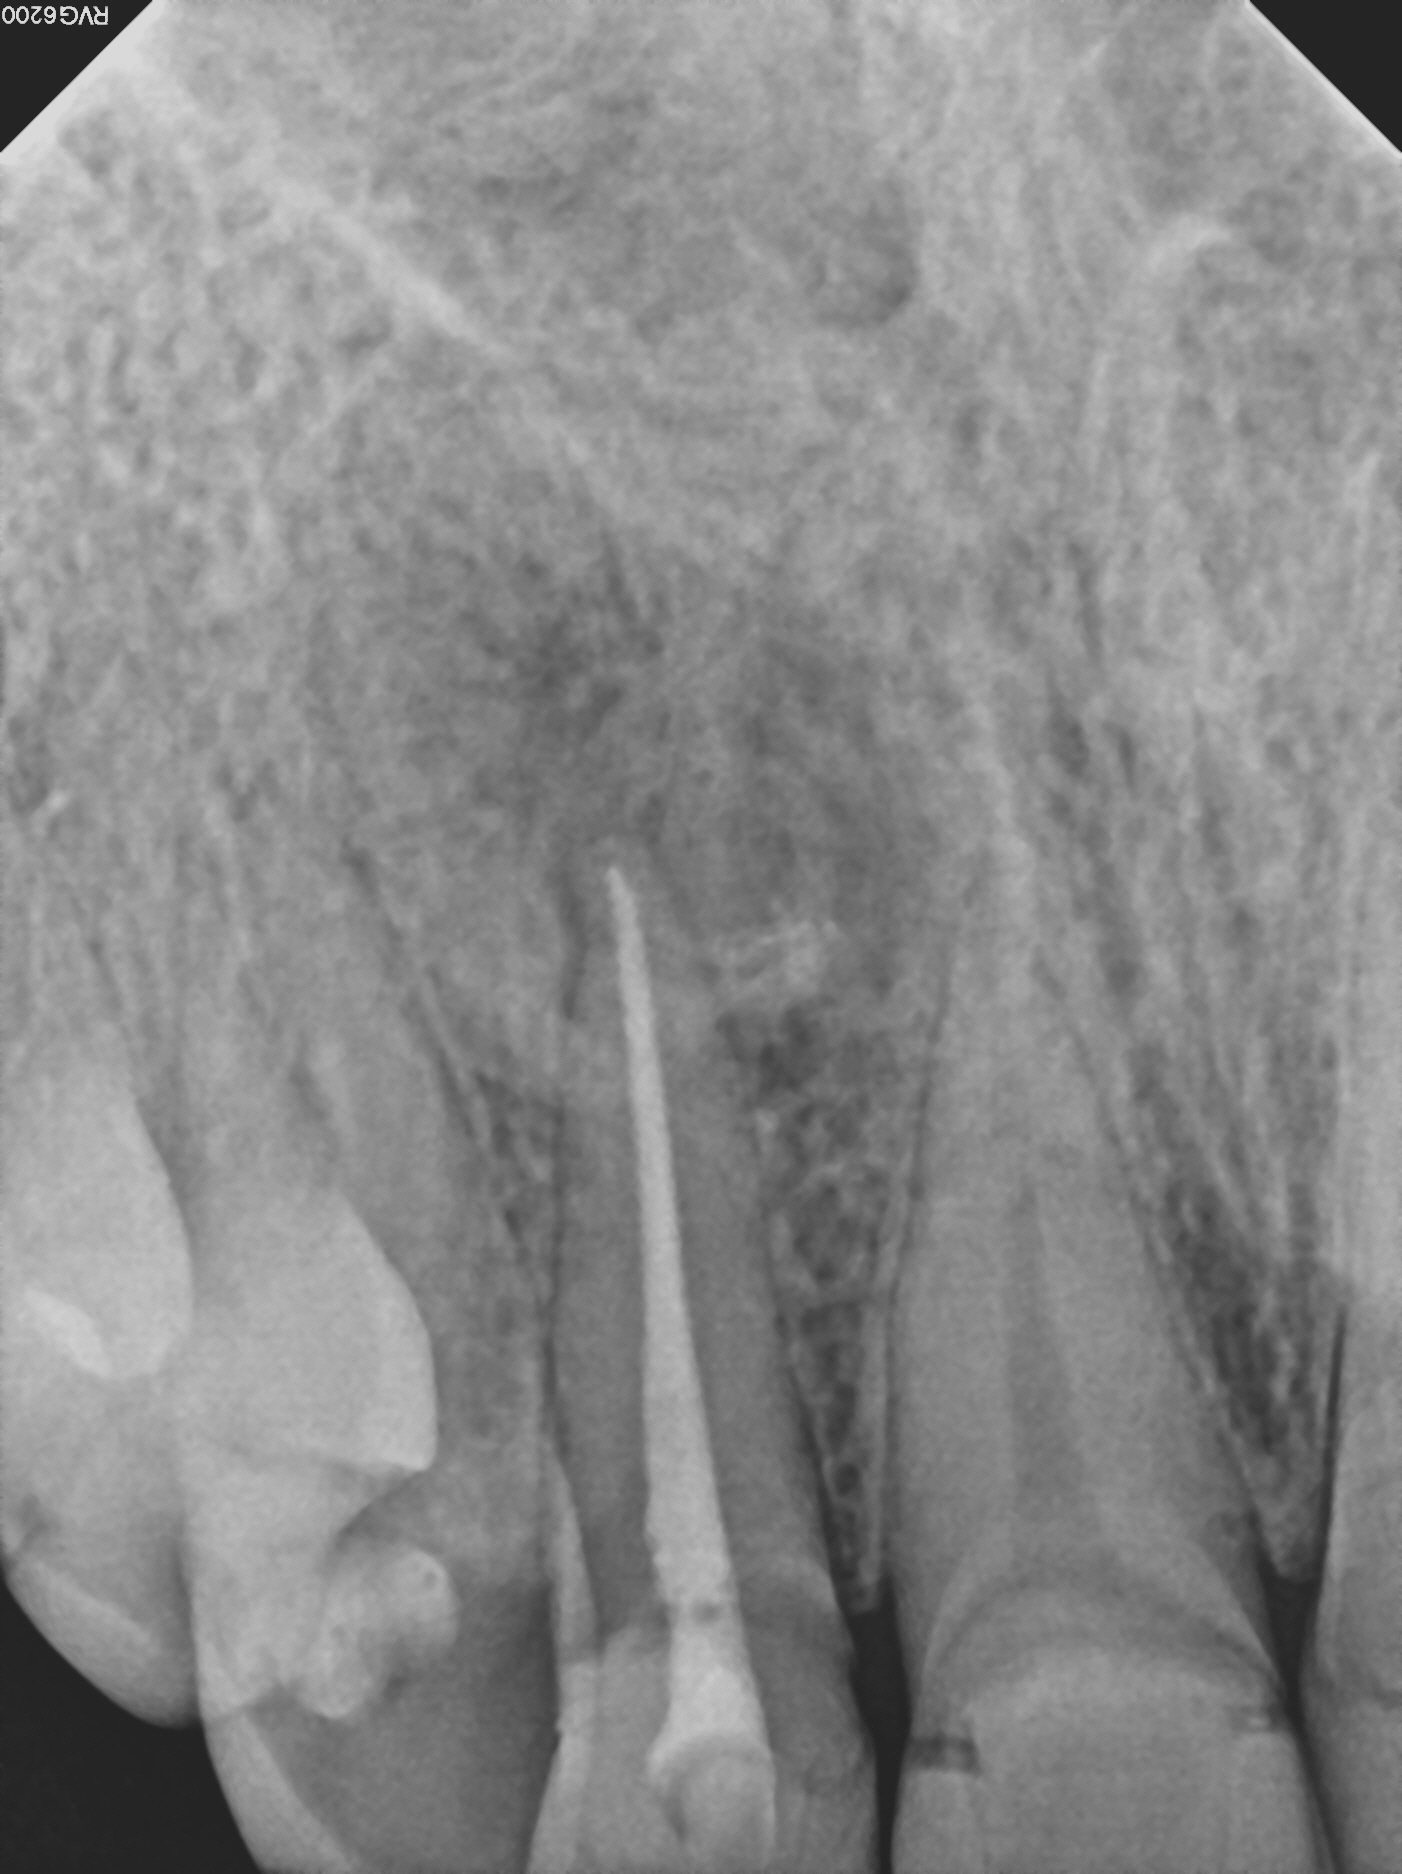

1_pre1

3_post1

Case 9

This case shows just how curved the roots of teeth can be, which can lead to the nerve canal spaces being difficult to fully treat. These types of cases are often referred to endodontic specialists for treatment due to the added complexity of the curved roots.